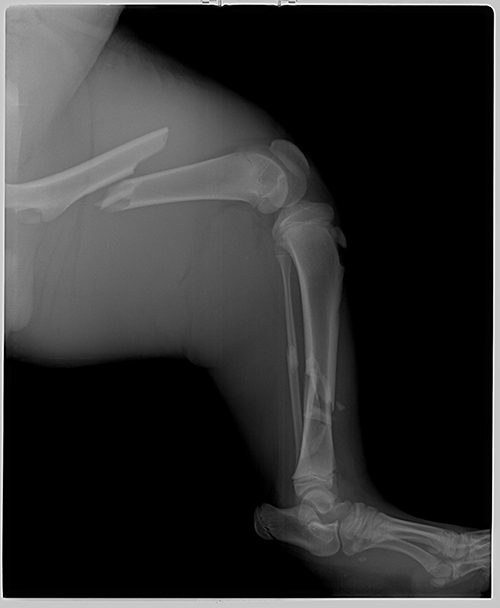

By day 14 our veterinarian felt he was strong enough to set his leg. Both large bones in his left hind leg were badly broken (see pictures above). The operation took almost five hours. She put rods through the center of the bones. It was a very big job, but everything went well.